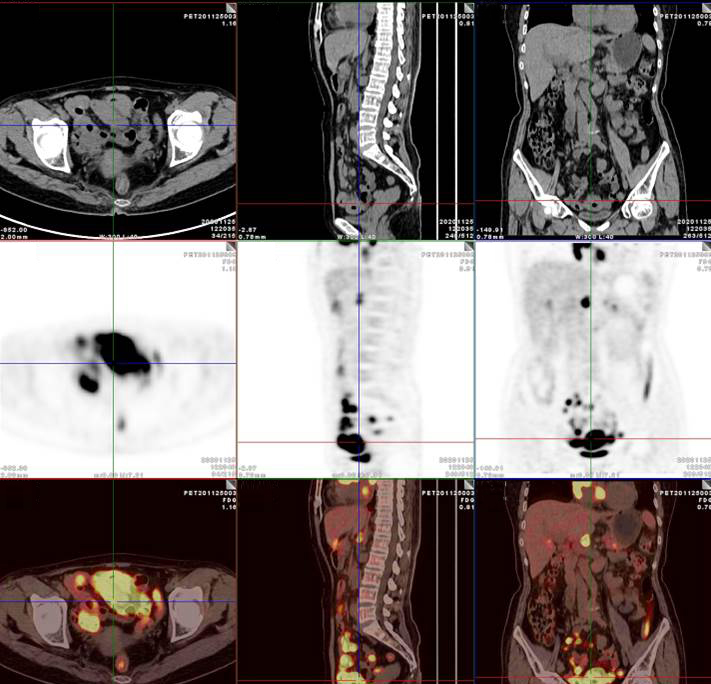

PET/CT影像圖

雙側(cè)腎上腺病灶、腹膜后淋巴結(jié)放射性攝取明顯增高

膽囊及雙腎上腺病灶、腹膜后淋巴結(jié)放射性攝取明顯增高

胃、雙腎上腺病灶、腹膜后淋巴結(jié)放射性攝取明顯增高

腸系膜多發(fā)淋巴結(jié)放射性攝取增高

多段小腸腸管放射性攝取增高

影像診斷

考慮淋巴瘤,請結(jié)合臨床病理